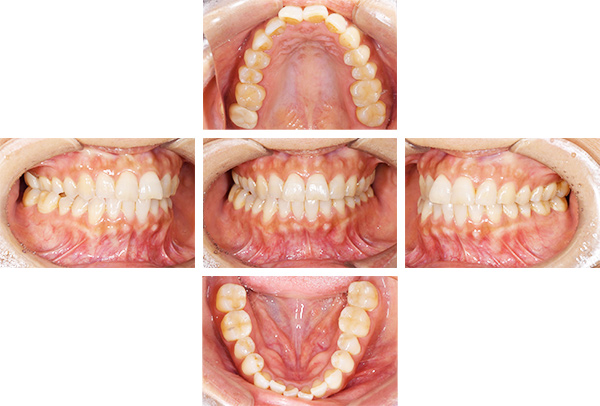

歯列矯正・インレー・クラウン症例

前歯が黒っぽいのが気になる、

悪いところは全部治したい

年齢 54代女性

主訴 歯をきれいにしたい

症例写真(治療前)

担当医師所見

治療前:

八重歯が目立ちます。また銀歯もおおく、見た目が気になります。虫歯も散見できます。

治療中

矯正装置をつけています。だんだん八重歯が動いてきているのがわかります。今回のケースでは、抜歯を行わずに矯正ができました。

症例写真(治療後)

治療後:

矯正治療と虫歯の治療すべて終わったときの写真になります。見た目も最初の頃とは全く違いますし、お口の中もすごく綺麗です。

治療

方針

まずは虫歯の治療を行い、被せ物をする部分は仮歯をいれて矯正を行う。矯正終了後、仮歯の部分を最終的な被せ物に変えていく。また気になっていた銀歯もセラミックに変えて終了となった。

内容

セラミックインレー、オールセラミックプレミアム、矯正